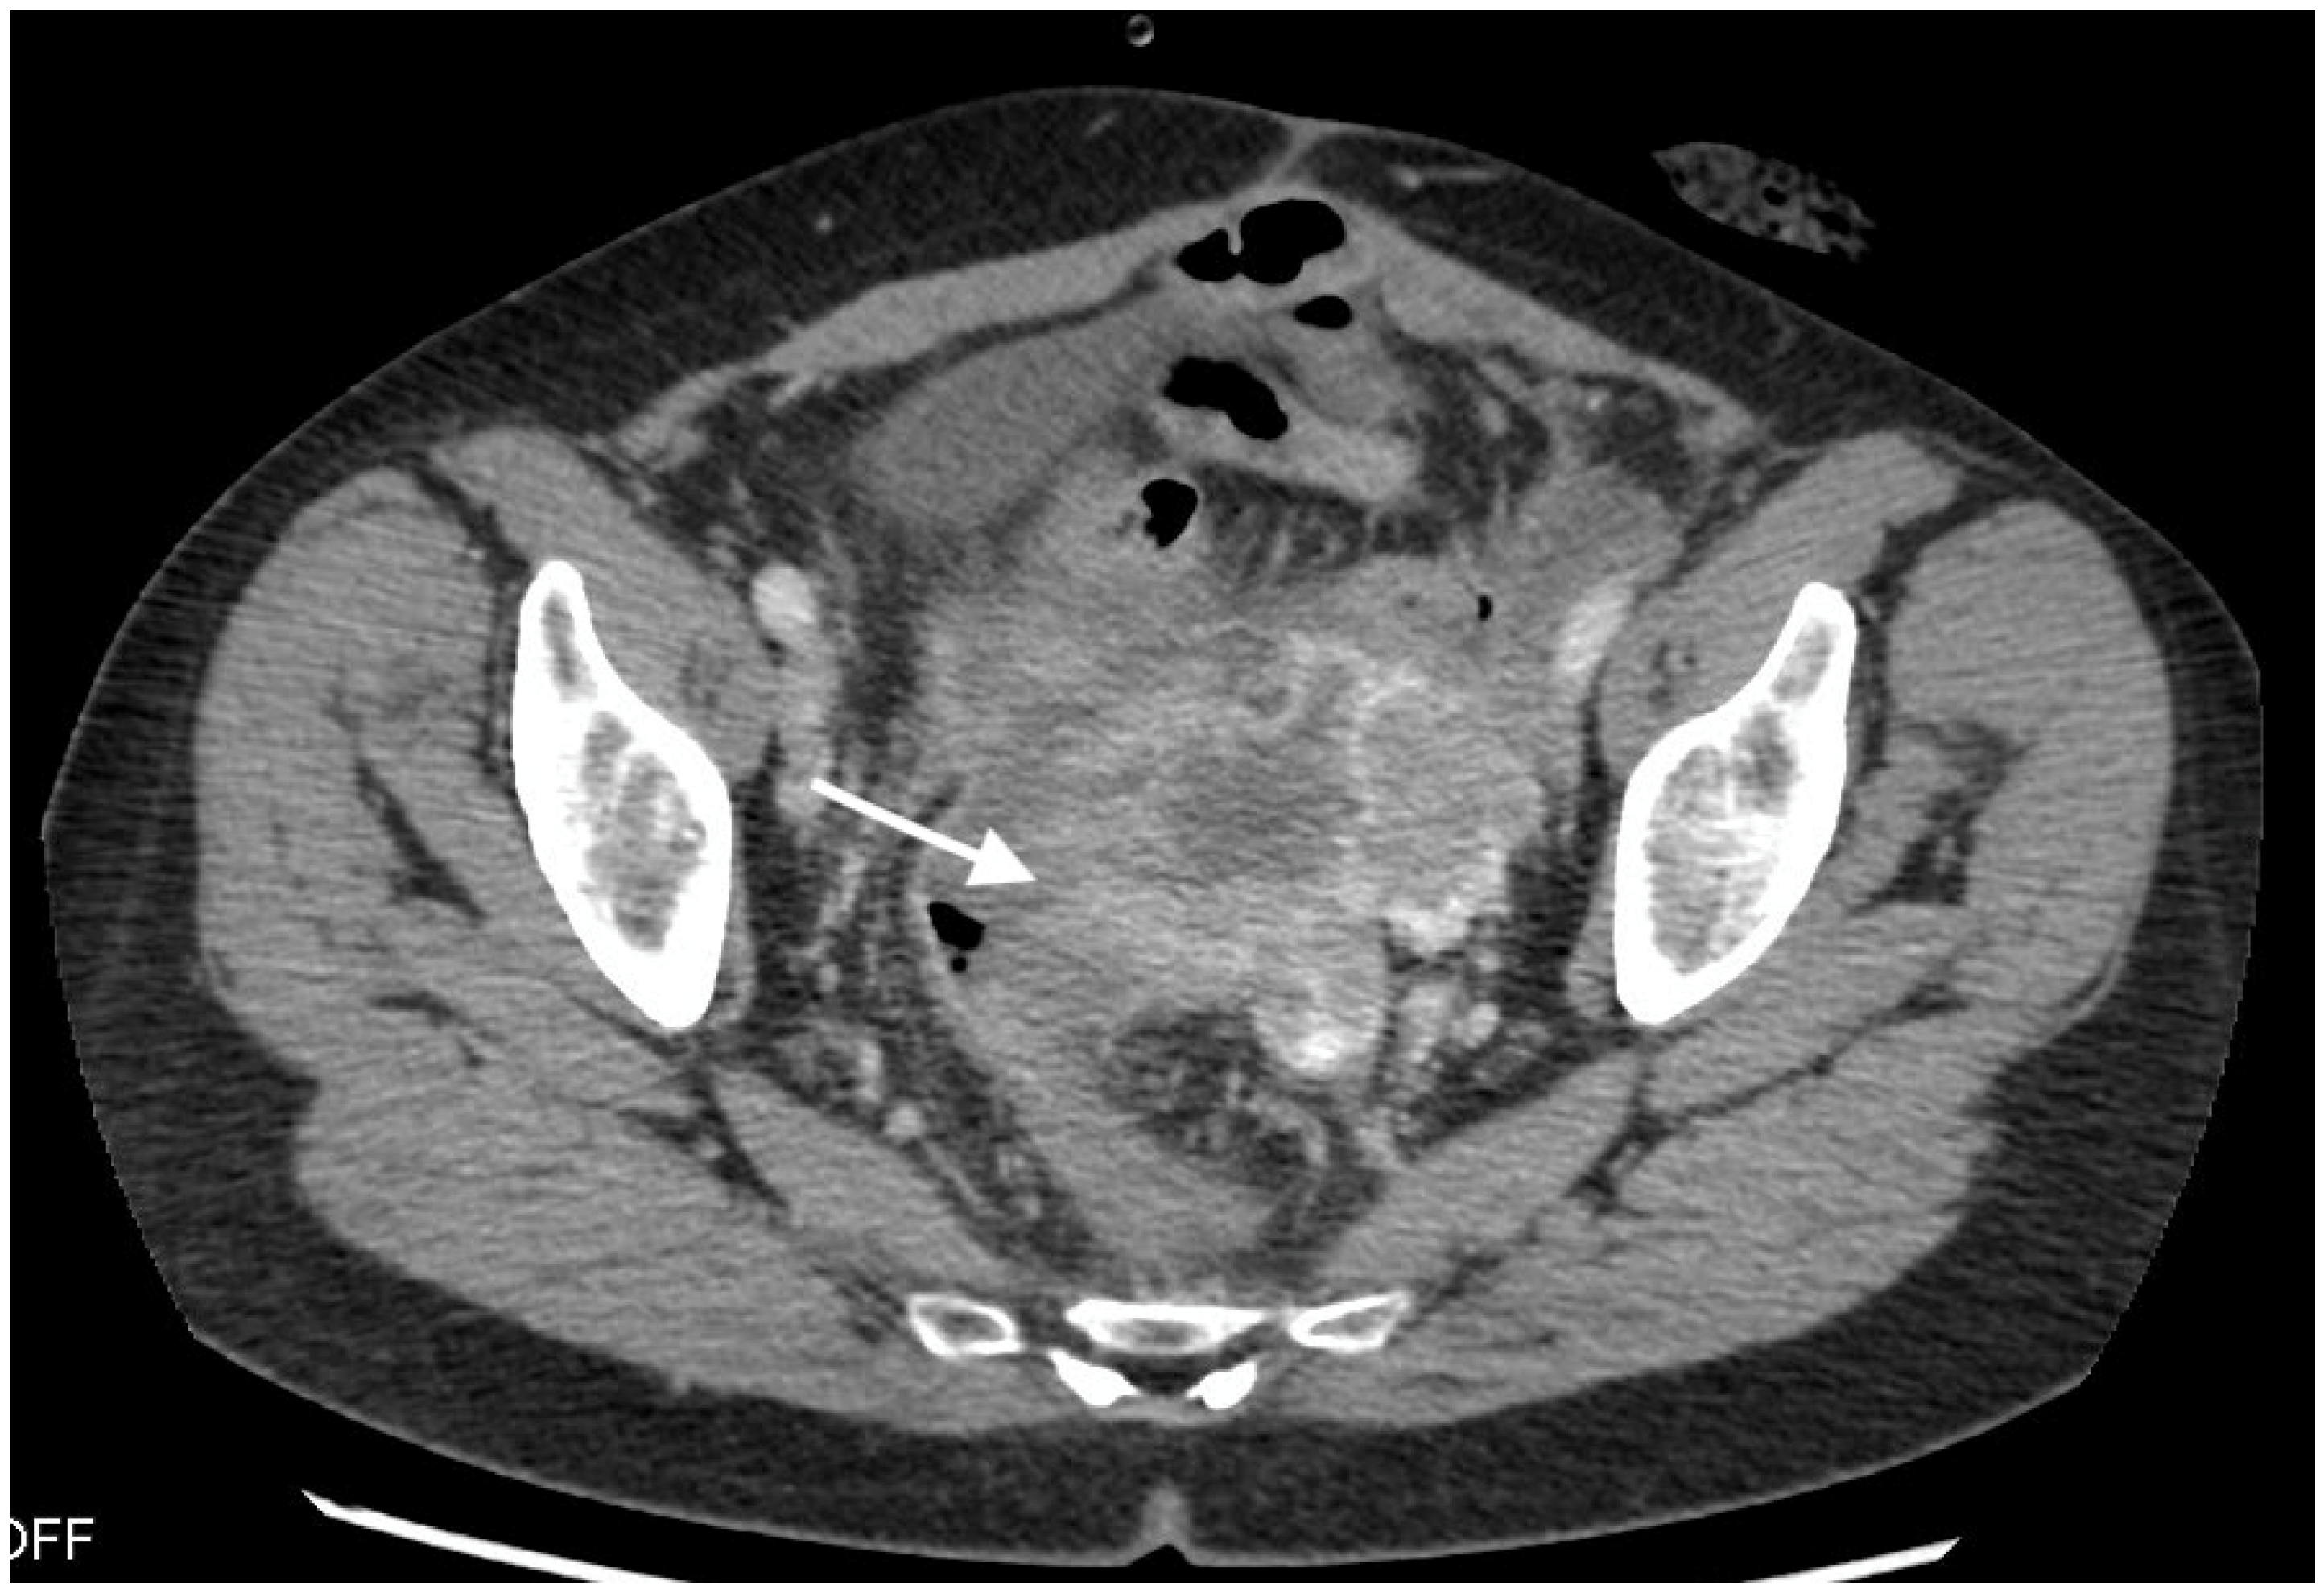

Figure 1.

Images from 58-year-old patient with carcinosarcoma of the ovary and recurrence in the rare form of giant cell carcinoma. The fistula between tumor and rectum (arrow), CT post-contrast image in venous phase obtained in the axial plane, shows pelvic tumor and adjacent intestine, fatty tissue between the tumor and intestine vanished as indirect sign of the fistula.

The median diameter of the relapsed tumor was 89 mm (range 36–130 mm). In all cases, fistulas formed between the tumor and large bowel. In three cases, fistulas formed between the rectum, including two between the sigmoid colon, one sigmoid and descending colon, one between the cecum and ascending colon, and one between the sigmoid colon and left ureter. On CT, in all cases, the fistulas were not directly visible, with only indirect signs of the fistula observed, such as infiltration of the intestine by the tumor, which we observed as vanishing of the fatty tissue between the tumor and the description of the intestinal wall, disruption of the intestinal wall, or the presence of gas in the tumor. In five patients, we observed thickening of the intestinal wall associated with a fistula (Figure 1, Figure 2 and Figure 3).

On computed tomography, we observed only indirect imaging signs of fistulas, such as infiltration of the intestine by the tumor, which we observed as vanishing of the fatty tissue between the tumor and the intestine, disruption of the intestinal wall, and gas in the tumor. Computed tomography’s limitation is evident when evaluating local tumor spread due to its lower soft tissue resolution. In other studies, CT was very useful for diagnosis, revealing indirect signs of fistulas, such as obvious thickening of the tumor wall and an air-fluid level within the tumor, suggesting that the ovarian tumor might have communication with the digestive tract; however, they also did not observe fistulas directly [11].